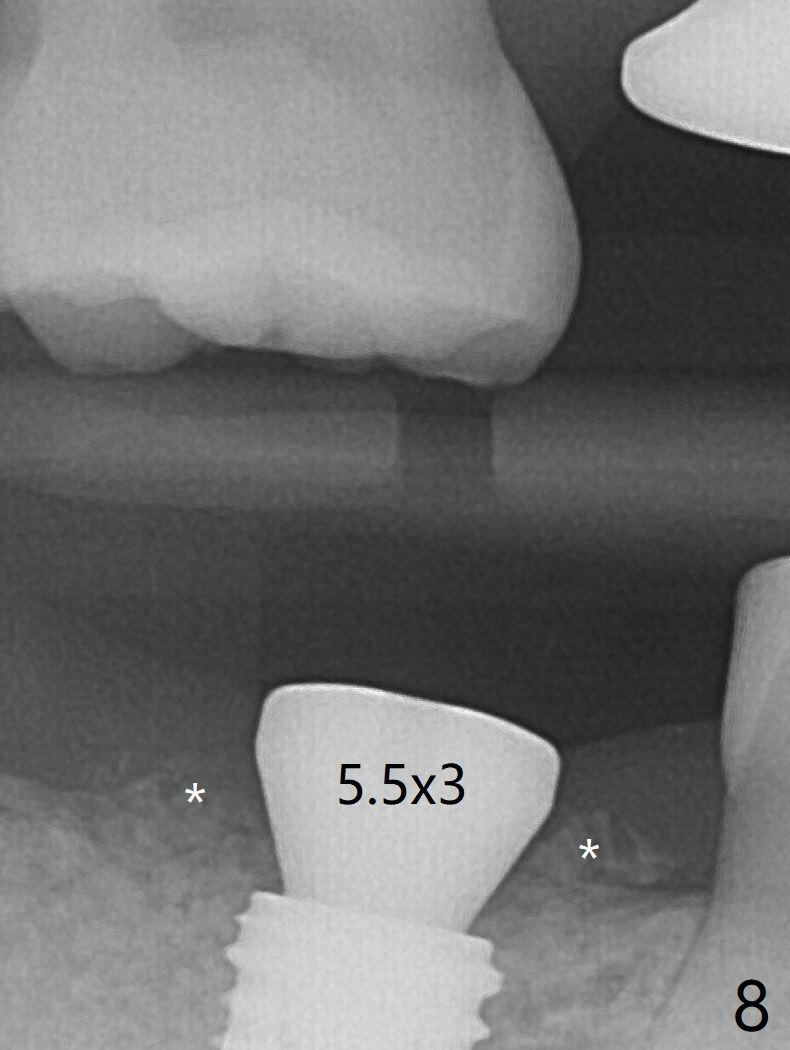

CBCT shows thin cortical bone formation mesiodistally 6.5 months post socket preservation with allograft with PRF at #31 (Fig.3 ^, as compared to Fig.1). The socket appears to be closing buccolingually 10 months postop (Fig.6 arrowheads, as compared to Fig.4). Bone density increases from 1100 units to 1,200-1,400 units 6.5 to 10 months. With underprep (4 mm), a 5x10 mm implant is placed with ~ 50 Ncm with guide (Fig.7). Following a 5.5 mm profile drill, a 5.5x3 mm healing abutment is placed (Fig.8); the implant plateau appears to be supported by the graft bone (*). The implant remains subcrestal 4 months postop (Fig.9).